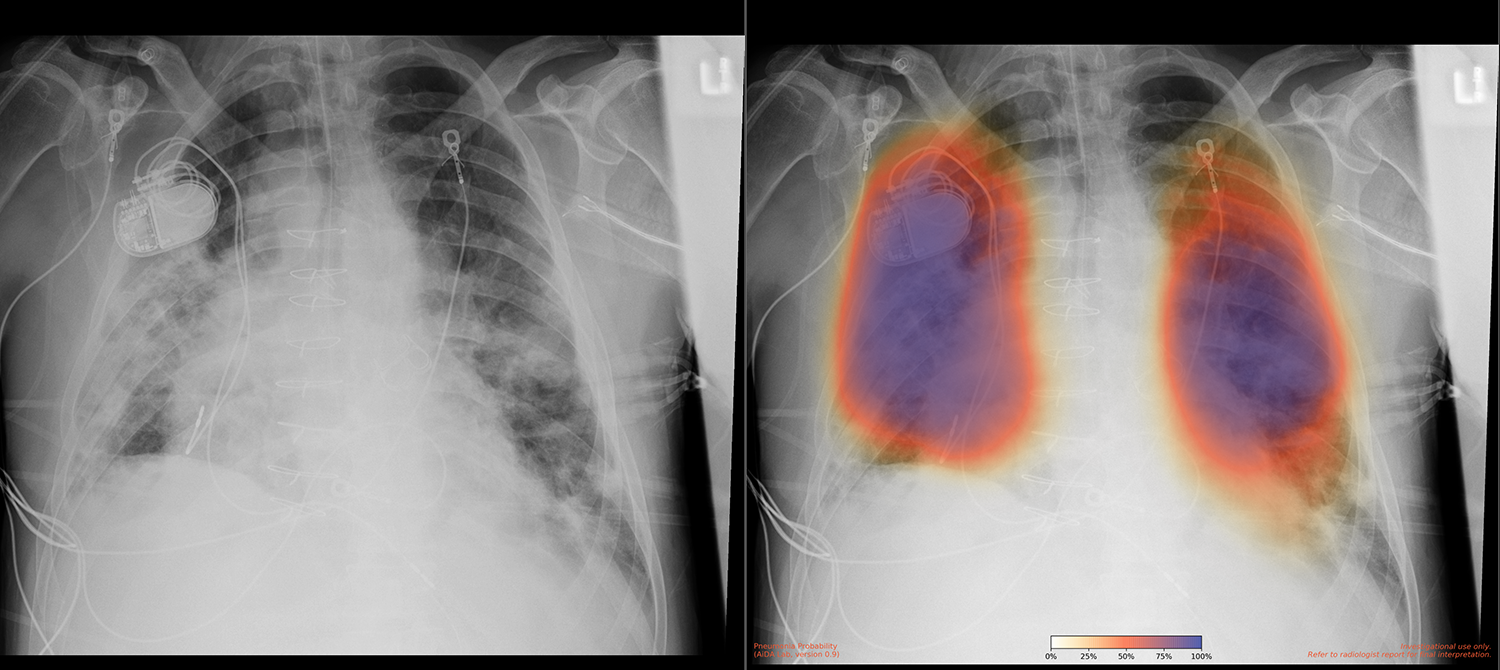

Developing an Innovative Pneumonia-Detecting Model

UC San Diego Health is among the top 15 research universities worldwide. The UC San Diego School of Medicine conducts hundreds of clinical trials each year, and the UCSD Health Services Research Center specializes in the collection and analysis of health outcomes data to support research. In 2018, a team from UC San Diego Health, led by Dr. Albert Hsiao, associate professor of radiology at the UC San Diego School of Medicine, developed a way to use machine learning to detect pneumonia in X-ray images. “We created a probability map with color coding that indicated how uncertain or certain a pneumonia was,” says Dr. Brian Hurt, a resident physician on Dr. Hsiao’s team. According to Dr. Hsiao, “What people typically do is create a model that gives a simple yes or no output, indicating whether it’s pneumonia or not pneumonia. But we felt that producing an image was important to highlight where abnormalities are.” The team published a paper on these results in early 2020.

The goal was to implement a system that could take in X-rays from a clinical setting, run the model on them, and return results quickly to assist with diagnosis. “A lot of models created in labs like ours are potentially promising but not very useful without actually building them into the clinical workflow,” says Dr. Hsiao. Such an implementation would potentially affect the diagnosis, treatment, and outcomes of COVID-19 patients. “The findings of COVID-19 pneumonia are basically the same as those of any other viral pneumonia,” says Dr. Hsiao. “The model that Brian trained performs well in this population because it’s a good model for detecting pneumonia in general.” The model was useful in two ways. First, if it detects pneumonia in an X-ray image, it prompts a test or retest in the event of a previous—possibly false—negative test result. Second, in patients with known infection, finding pneumonia on an X-ray could indicate the illness’s severity and prognosis, informing treatments.

The UC San Diego Health research team had already set up the model to take in images and return them with a color-coded overlay. It only needed a cloud solution that could connect to the clinical imaging system to receive the images and output them directly into the patients’ files, making the images convenient for medical professionals to access and view. Because the team had already created HIPAA-compliant environments on AWS, it was able to get the project up and running in a mere 10 days. “The first day it was running on AWS, the model processed around 400 X-rays with very few glitches,” says Dr. Hogarth. In the next 6 months after implementation, the model processed over 65,000 X-rays, each in 3–4 minutes.

A side-by-side comparison of a chest X-ray image: the left shows a standard medical X-ray with visible internal medical devices, while the right displays the same image with an AI-generated heatmap overlay indicating the probability of pneumonia in different lung regions.